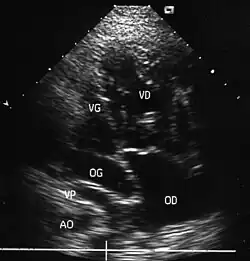

- L'échocardiographie qui est de plus en plus l'examen pratiqué en première intention. Cet examen permet d'affirmer le diagnostic en montrant les anomalies anatomiques, d'apprécier le caractère plus ou moins fonctionnel des shunts cardiaques fœtaux, de rechercher d'autres anomalies associées et dans une certaine mesure d'apprécier le retentissement de la malformation.

- Les coupes échographiques les plus utiles à cette fin sont :

- La coupe parasternale gauche grand axe : elle montre que le vaisseau issu du ventricule gauche (le plus postérieur) se dirige anormalement vers l'arrière et se bifurque précocement. C'est donc le tronc pulmonaire et non l'aorte comme normalement.

- Les coupes sous costales qui montrent bien le trajet parallèle des gros vaisseaux et leur inversion. Cet examen permettra d'éliminer en particulier un retour veineux pulmonaire anormal total bloqué qui aurait pu rendre compte de l’hypervascularisation pulmonaire sur la radiographie des poumons.